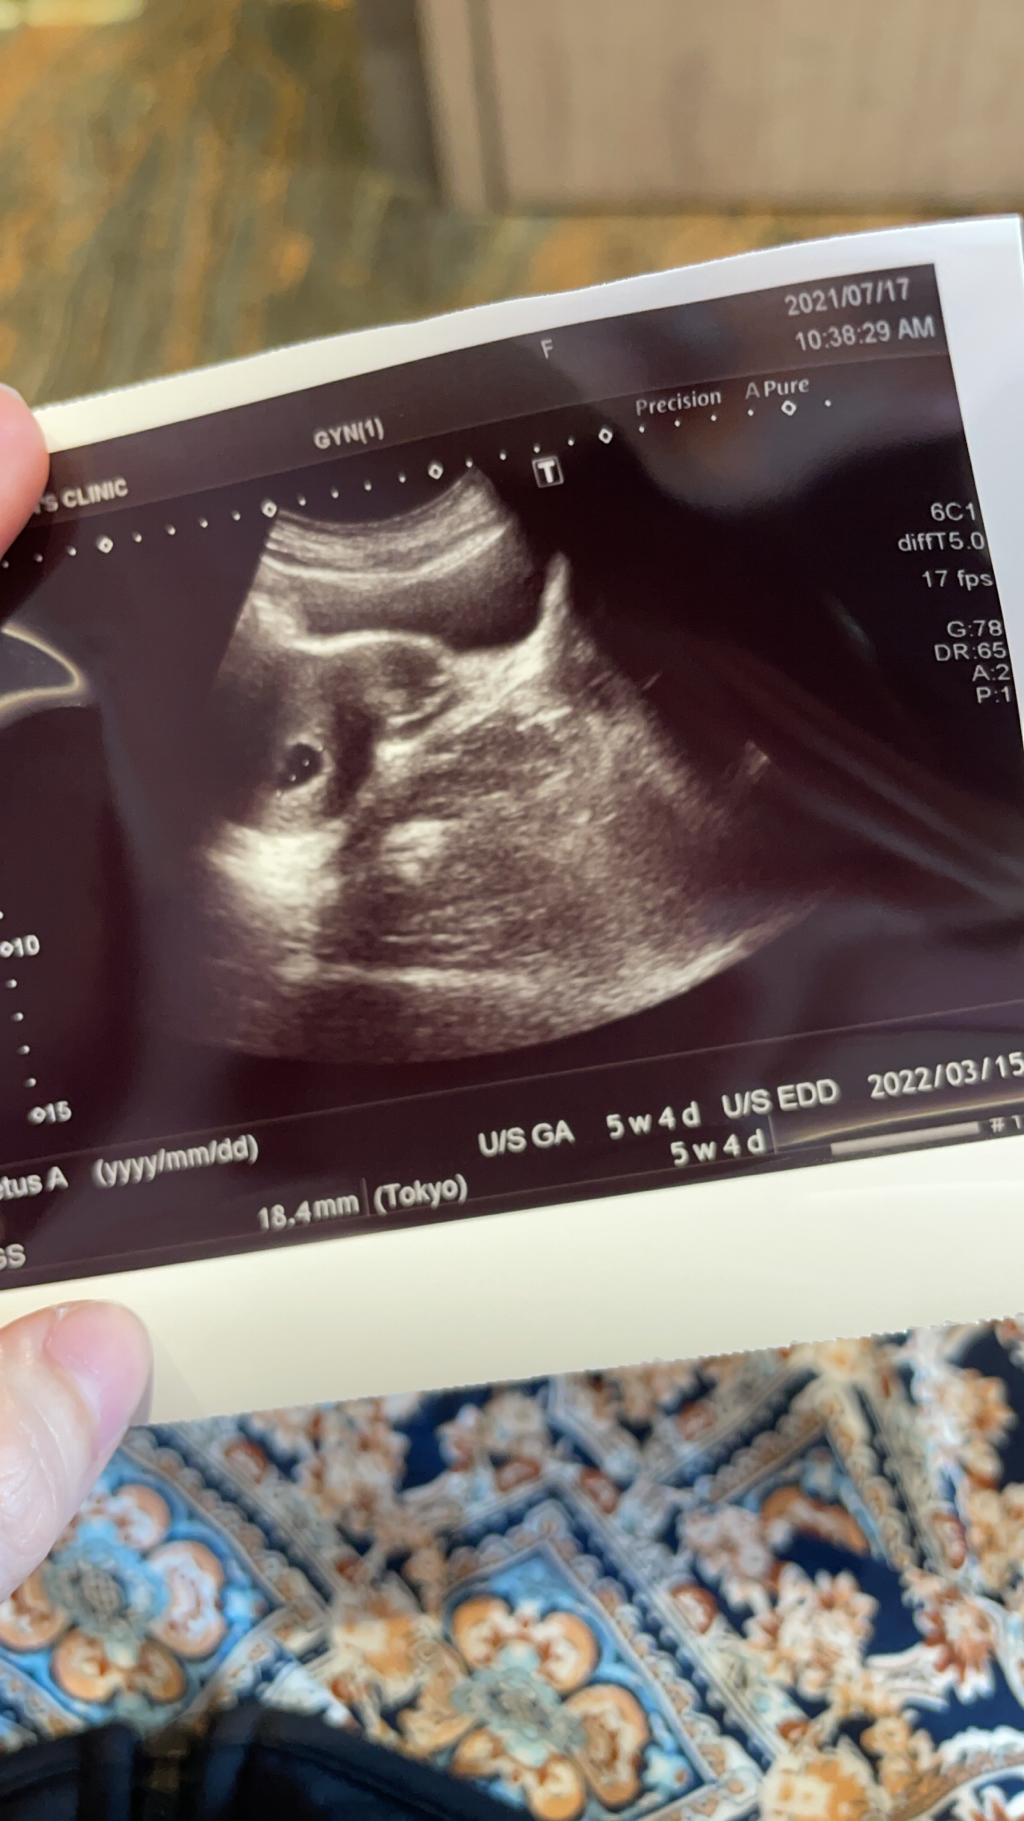

7/17,微出血,一絲鮮血跟咖啡色,去附近產檢(附圖1.84cm)胚囊有長大,開白色小球安胎藥